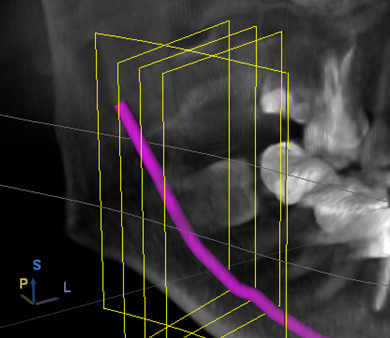

3-D navigierte Implantation

Mit unserem speziellen Planungssystem können wir schon vor einem Eingriff feststellen, wieviel Knochen zur Verfügung steht. Anschließend planen wir virtuell die richtige Position der Implantate.